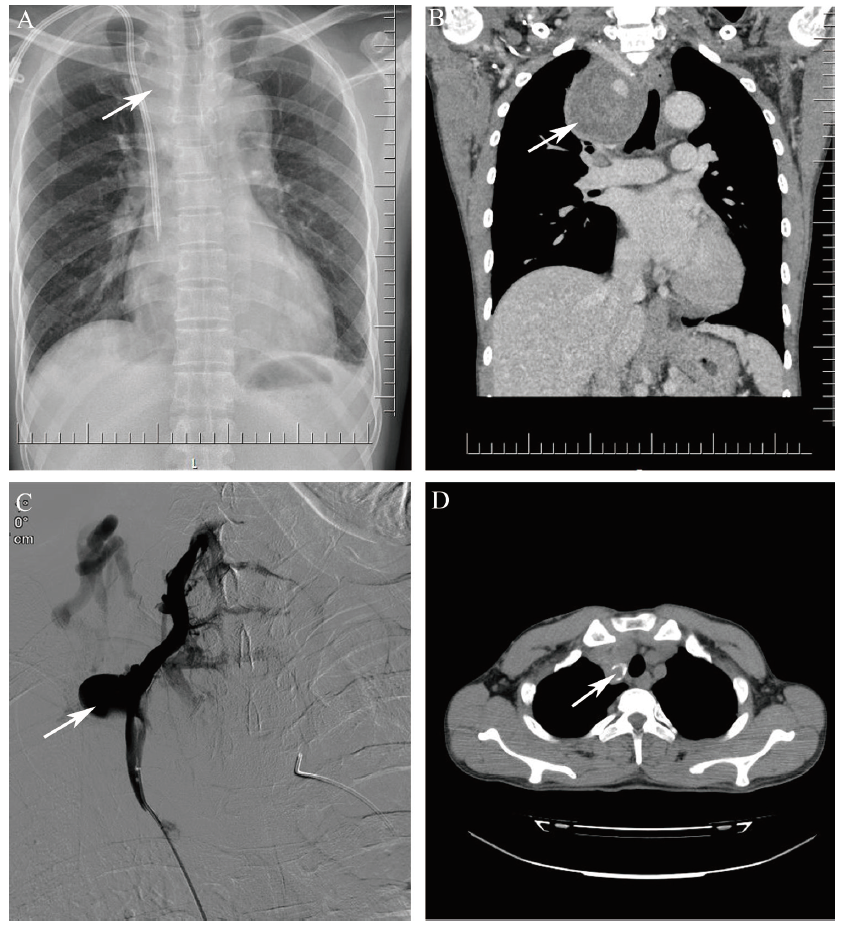

患者男,45岁。因呕吐、乏力、气促2个月于2019年1月31日入院,诊断为“慢性肾炎、慢性肾脏病5期、肺部感染、慢性心功能不全”,需有隧道涤纶套导管(TCC)为过渡性通路行血液透析[1,2]。在超声引导下穿刺右侧颈内静脉,术中患者称右胸痛而停止手术,未置入导管,观察手术局部和全身均无肿胀、渗血等异常,1周后再次在超声引导下穿刺,顺利置入1条美敦力palindrome 36 cm导管,术后次日胸片显示沿右侧颈内静脉入口穿刺点到第4肋纵隔内4 cm×5 cm血肿,导管尖端位于右心房中部(图1A),导管行程流畅,颈部无红、肿、痛及气管偏移等症状,未重视和追踪;患者因导管透析3个月导管功能良好、全身状态及心肺功能改善,拟建立AVF。因左前臂中段头静脉塌陷,并呈网状分布,考虑后期内瘘成熟困难,予建立右腕部R-C AVF。术后1个月余右上肢浅表静脉曲张并逐渐出现肿胀,伴间断胸痛、胸闷、气促,疑TCC导致内瘘流出道狭窄,拔除TCC启用AVF行血液透析,上述症状暂时缓解,20余日后因“气促及右上胸痛加重、伴右上臂轻度肿胀”步行入院。

图1 一例血透患者右无名静脉损伤后超长时活动性出血的胸片、DSA及CT图

注:A为2019年2月8日(胸片置管次日)可见纵隔血肿(箭头所示);B为2019年6月15日CT纵隔血肿(箭头所示) 66 mm×60 mm,气管左偏;C为2019年6月15日DSA造影见右侧无名静脉约2 mm直径小孔活动性出血(箭头所示),颈部浅表静脉怒张;D为2020年3月25日CT见纵隔包块(箭头所示)吸收、钙化,右侧无名静脉闭塞。

CT显示右上纵隔血肿,气管左偏(图1B),数字减影血管造影(DSA)造影发现右侧无名静脉侧壁有2 mm左右小孔活动性出血,颈部浅表静脉怒张(图1C),彩色多普勒超声(彩超)也显示类似结果(图2A)。

诊断:慢性肾脏病5期;右无名静脉针刺伤伴活动性出血;纵隔血肿。患者因经济困难不同意置入覆膜支架止血治疗;为减轻动静脉内瘘建立后左向右分流对中心静脉产生的压力、减少出血,急诊行“右腕部动静脉内瘘结扎术”,以右侧股静脉TCC行无肝素血液透析,血压控制在正常范围,减少容量负荷,严密观察相关症状、体征,反复复查胸部增强CT和颈部血管超声1月余,患者症状无加重、胸部CT血肿无增大、颈部血管超声活动性出血停止(图2B)后转门诊;依然不定期检查胸部CT和血管超声,右纵隔血肿缓慢吸收变小,患者日常生活等无影响。13个月后彩超(图2C)及增强CT检查(图1D),右无名静脉闭合,纵隔血肿减小到2.9 cm×2.8 cm并部分钙化,予左腕部建立R-C AVF并顺利成熟使用。18个月后再次彩超示血肿进一步缩小、钙化(图2D)。